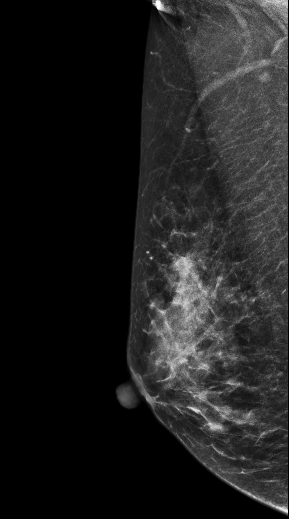

DBT图像:

影像描述: 在2DMLO位图像的上象限发现一不对称局限性致密影,但CC位上未见明显异常病变区域,在V-Preview图像上MLO位上病变显示明显逼2D更清晰,在CC位上乳头后方深部我们可以清晰的发现病灶,在3D-plane图像上我们可以更进一步清楚观察到病变形态大小范围,以及病灶边缘呈星芒样长短不一毛刺样改变。 影像诊断: 右乳偏外象限局限致密影,考虑BI-RADS 4B 。 病例点评: 病理证实右乳浸润性导管癌,DBT可以给我们提供更多诊断信息有助于明确病变性质。